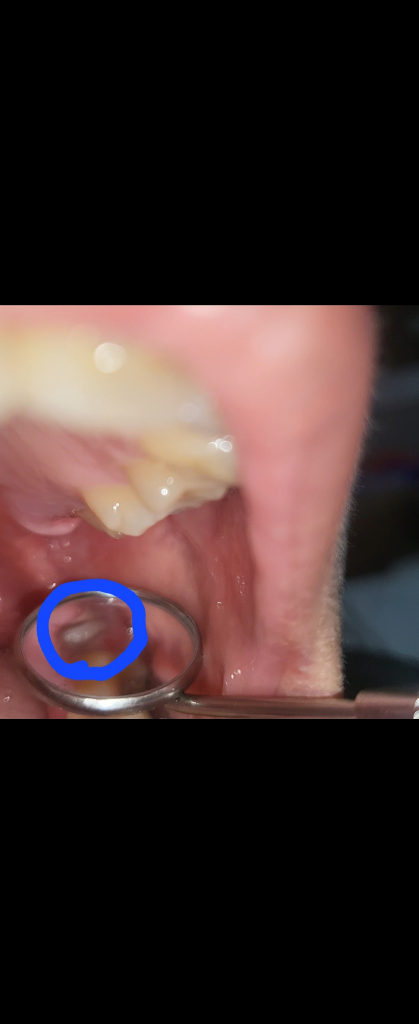

하얀막은 상피세포이므로 걱정하지 않으셔도 됩니다. 드라이소켓은 극심한 통증을 유발하므로 걱정하지 않으셔도 됩니다.

하얀막은 잇몸이 치유되는 조직으로 보입니다..혈병이 떨어진다고 해서 무조건 드라이 소켓이 발생하는것은 아니니 염려 안해도 될것 같습니다.

드라이소켓은 감염의 일종으로 냄새가 많이 나고 엄청난 통증이 동반됩니다. 저부분은 염증이 아니고 발치하고 나서 생기는자연스러운 현상입니다.